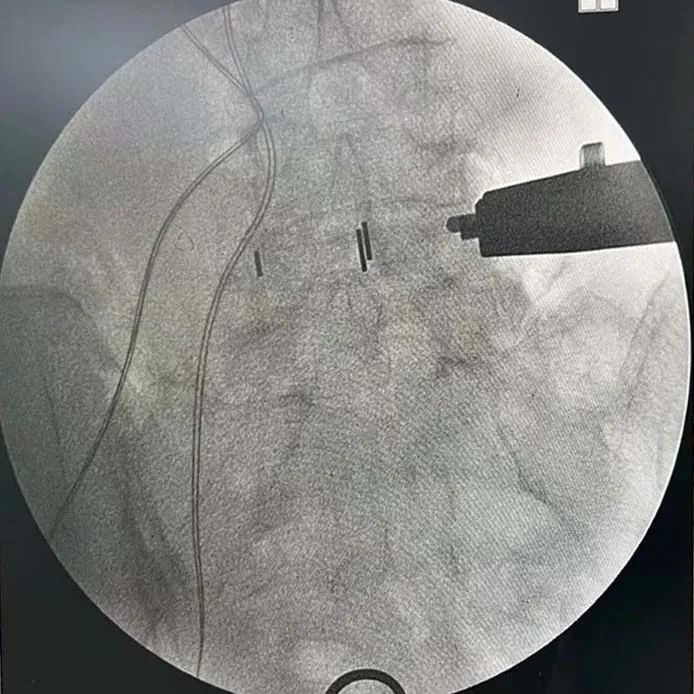

透視確認(ren)手術節段(duan)——

植入(ru)融合器,透視確認融合器位(wei)置——

透(tou)視確認固(gu)定夾——

插片融合器植入前后影像對(dui)比——

椎間隙高度撐開效(xiao)果顯著,椎(zhui)間孔空(kong)間恢復明顯

取(qu)下插(cha)片融合器把持(chi)器,透視(shi)最終效果——